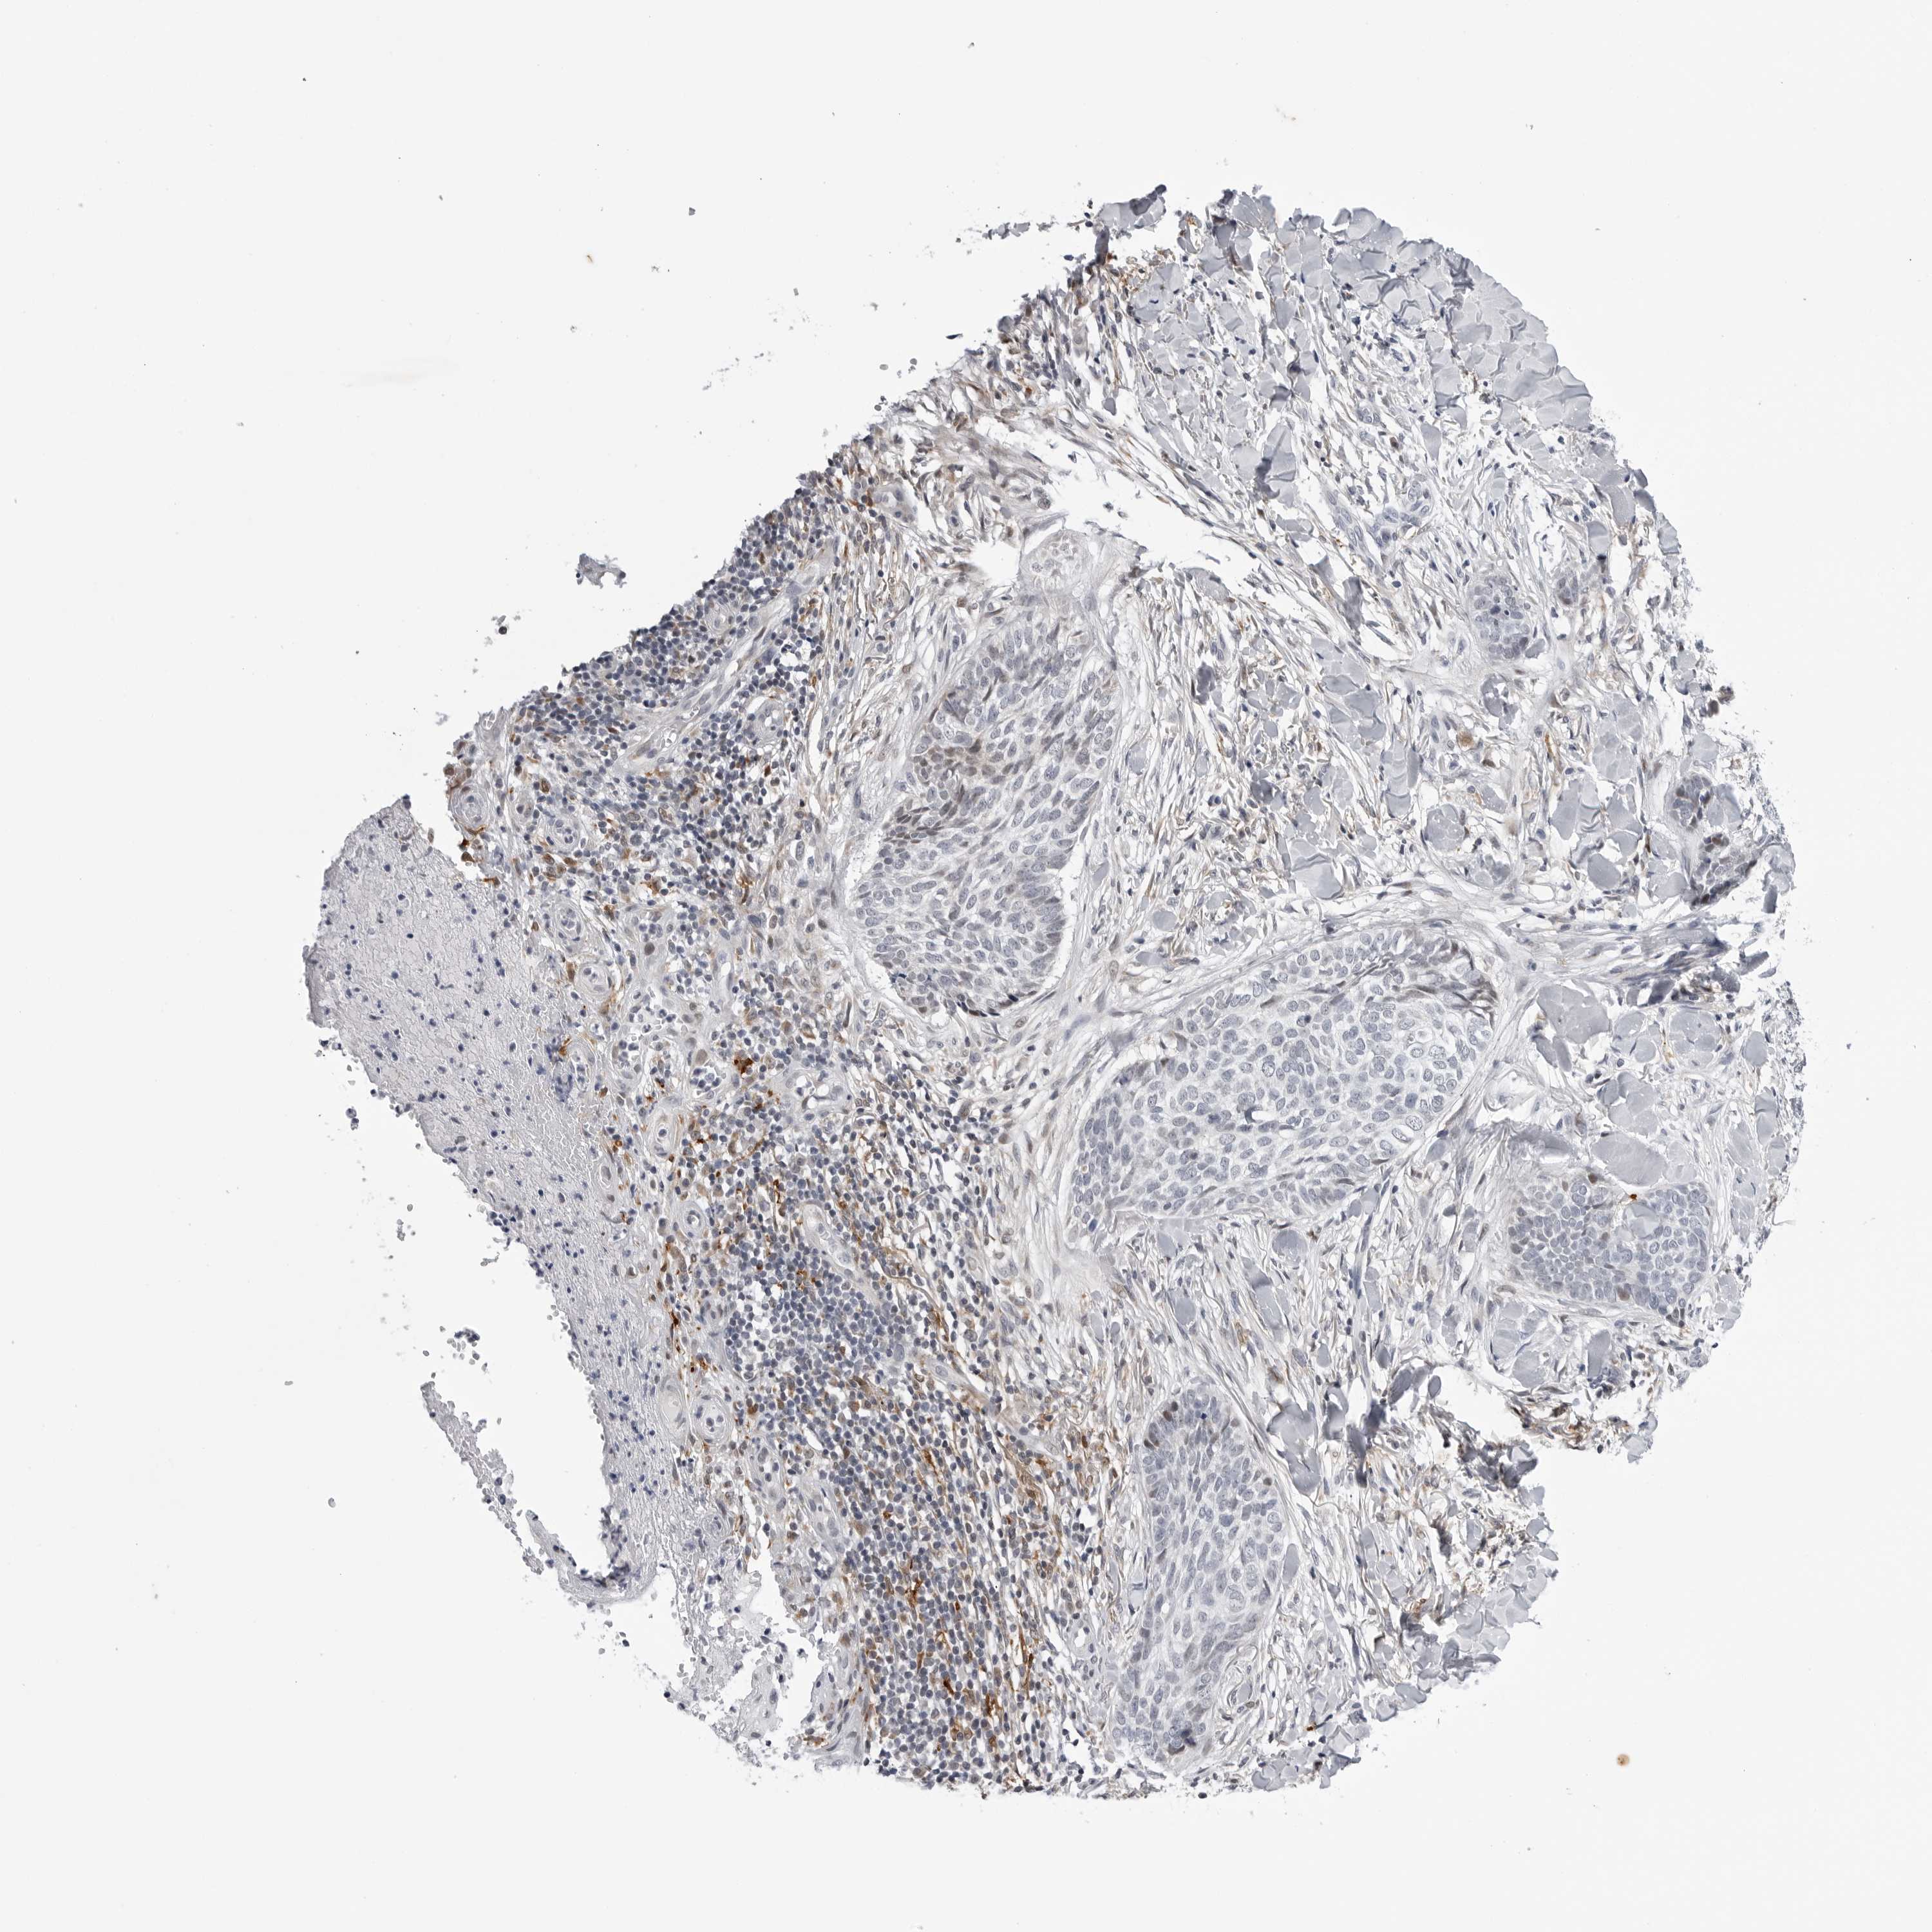

SKIN CANCER - Protein expressioni

A mouse-over function shows sample information and annotation data. Click on an image to view it in a full screen mode. Samples can be filtered based on level of antibody staining by selecting one or several of the following categories: high, medium, low and not detected. The assay and annotation is described here.

Each image is clickable and will lead to virtual microscopy that enables deeper exploration of all samples and also displays staining intensity scores, fraction scores and subcellular localization as well as patient and tissue information for each sample.

Antibody HPA027401

Squamous cell carcinoma, NOS